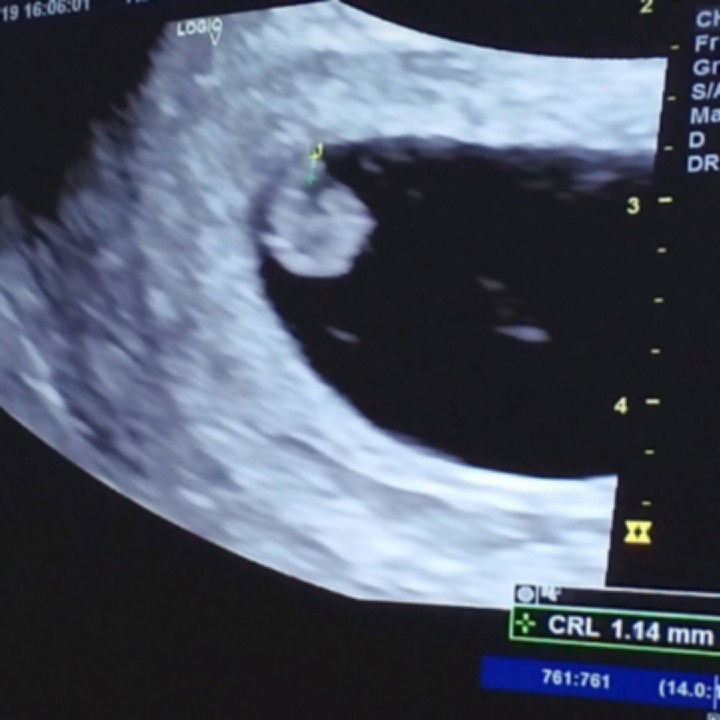

Ok naman po ang heartbeat ni baby pero mahina ang kapit. This is my first time na mabuntis at after 3years ngayon lang kami magkakababy ni mister. Please sama niyo po kami sa prayers niyo na after 2 weeks na bed rest ko e maging ok na ang baby dahil sa iinumin kong pampakapit na bigay ni ob ko. Maraming salamat po!